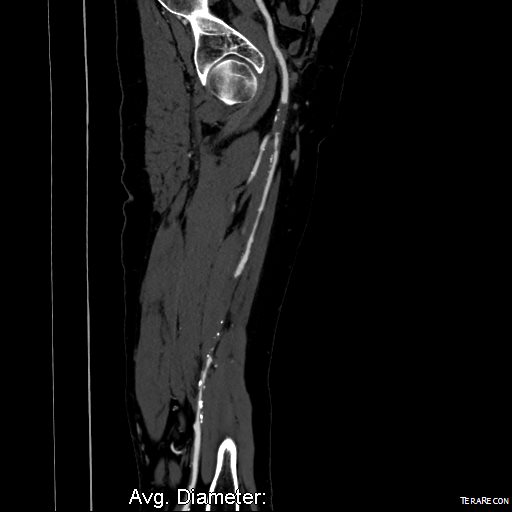

At one point in recent years, I saw a patient who had an axillary artery to anterior tibial artery bypass with PTFE (figure above). That was a kind of marvel to me, but my initial response was a bit of a sneer.

Giving it some thought, the rationale could have been to spare the patient from a hip disarticulation as the patient had had failed revascularizations and was occluded from the infrarenal aorta to the anterior tibial artery on that side. If you see such a thing, it sparks wonder as it feels both wrong and splendid at the same time because some surgeon had the audacity to pull it off. By the time I saw it, the patient had avulsed the proximal anastomosis, infarcted their leg to their thigh, and was headed for a hip disarticulation, four years after the creation of the bypass. Four years of patency!

On examination, he had heavy scarring in both groins from prior open incisions healed by secondary intention, a midline laparotomy incision. He had weak bilateral axillary and brachial artery pulses. He had no pulses in either leg. The right foot had gangrene of the distal phalanx of the third toe. The both feet were anemic and painful -the left foot had more dependent rubor. Pulse volume recordings were flat in both legs. TCPO2 was in the 20-40mmHg range at the thighs bilaterally suggesting reduced potential for healing an above knee amputation. Vein mapping showed no suitable saphenous vein in either leg. CTA (figure below) showed both external iliac arteries to be occluded or absent and the common femoral arteries to be occluded or missing bilaterally.

The left femoral bifurcation was preserved and the left SFA was patent into small underfilled tibial vessels. On the right, there was an isolated segment of profunda femoral artery that reconstituted from pelvic collaterals. The right below knee popliteal artery reconstituted and had underfilled but patent three vessel runoff (figure below).